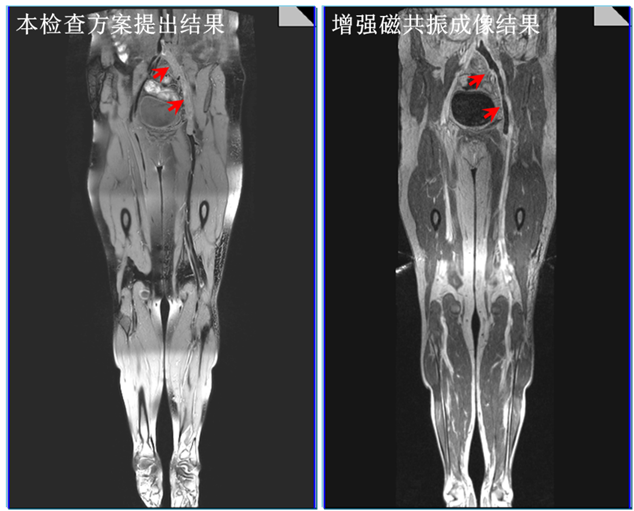

2. 不同时期血栓病人的成像结果比较,本项目提出的检查方案可以通过血栓的定量测量推出血栓的进展和分期,为临床精准化治疗提供依据